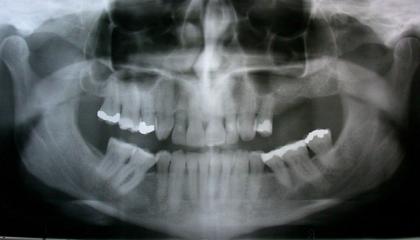

Before